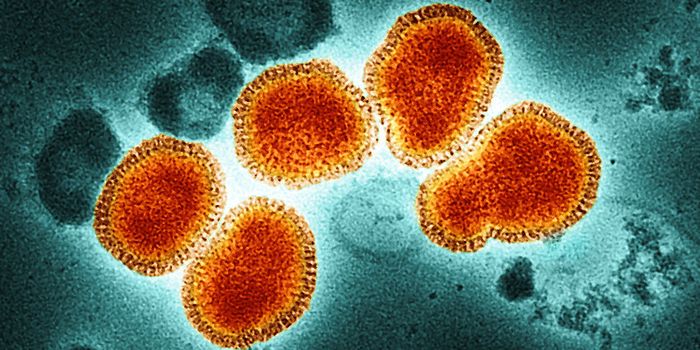

JUL 29, 2024MicrobiologyThe H5N1 avian influenza is highly pathogenic and has been devastating bird populations worldwide. It continues to ...

JUL 28, 2024MicrobiologyHighly pathogenic avian influenza could once only be caught from an infected bird. But it seems the virus can now move f ...

MAY 28, 2024MicrobiologyThe US Centers for Disease Control and Prevention (CDC) is tracking H5N1, an avian influenza that has wreaked havoc on b ...